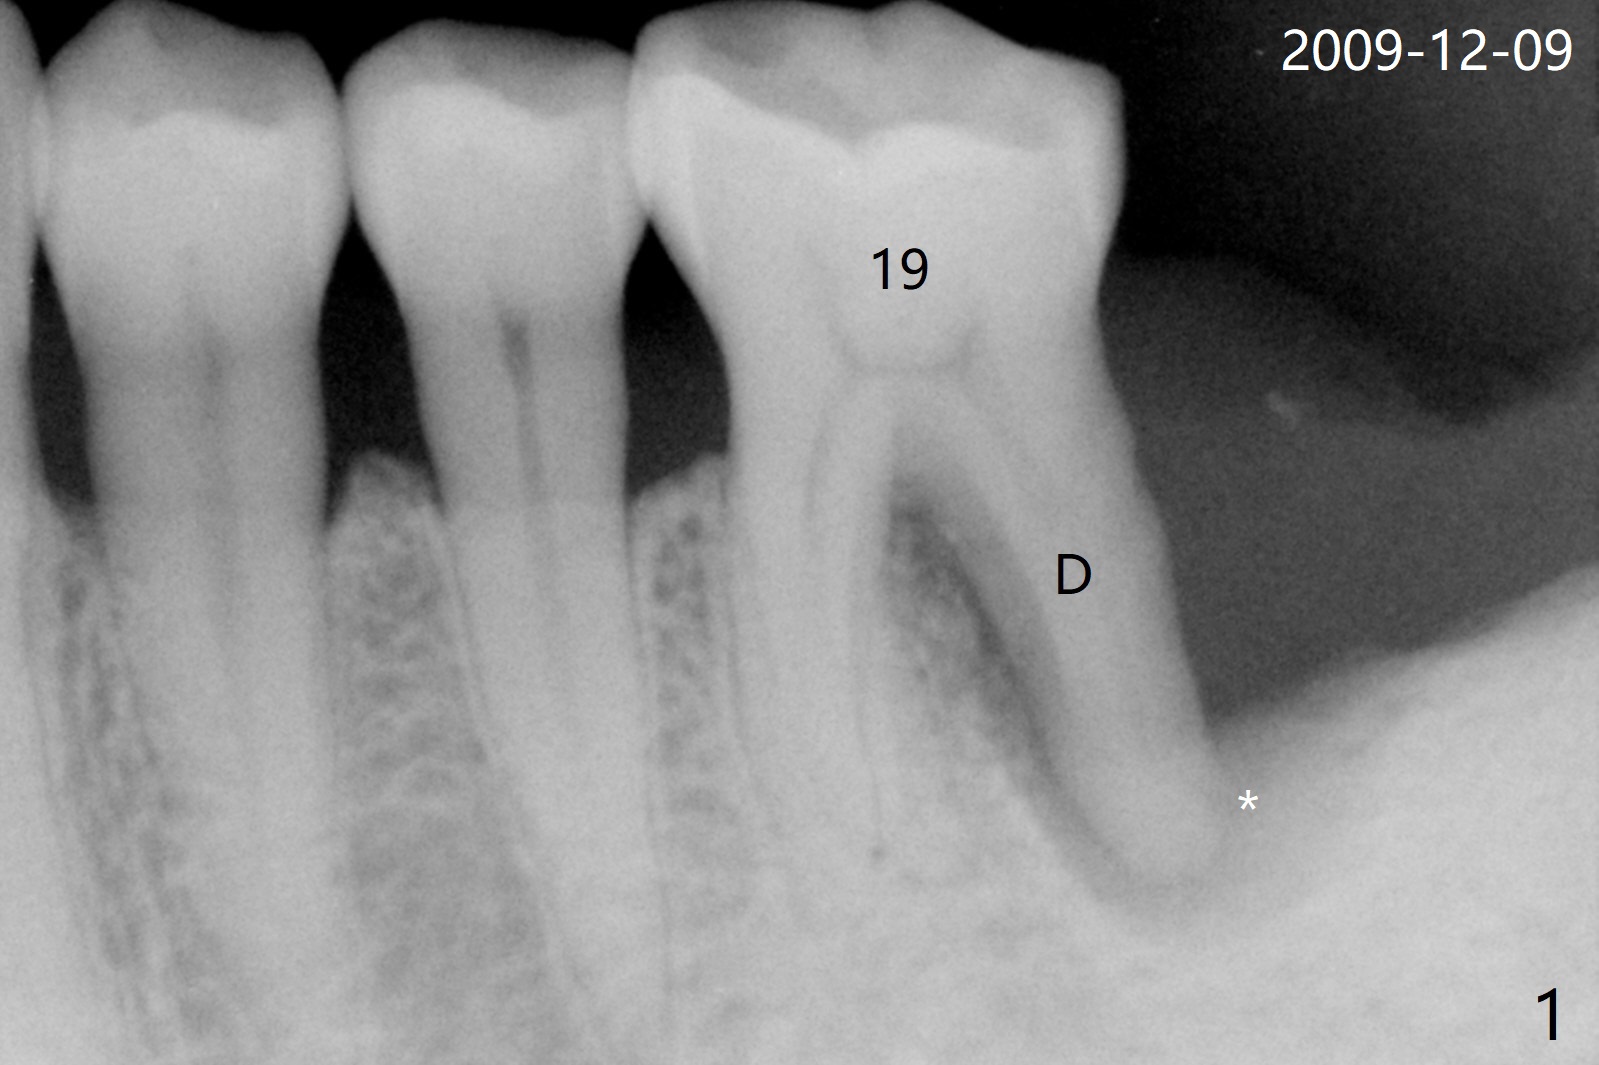

A 56-year-old man had distal gingival erythema at #19 with a fistula (Fig.1). Upon opening the pulpal chamber, the pulp is vital in the mesial canals, while necrotic distal. Root canal therapy is finished 1.5 months later (Fig.2). Although the patient was pleased with the treatment, the gingival infection and fistula did not improve. The tooth mobility increases over the years (Fig.3). He will return for evaluation next Monday. What should be done?